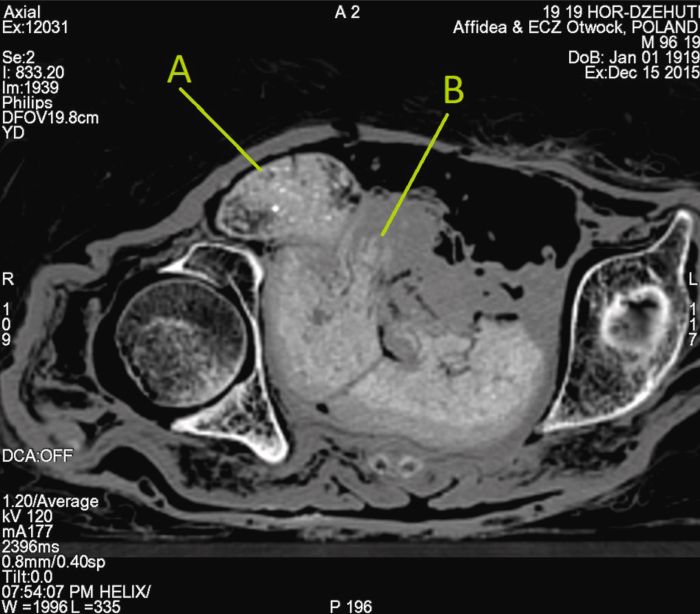

picture Рентген і КТ черевної порожнини мумії з виявленням плодуФото: Science alert